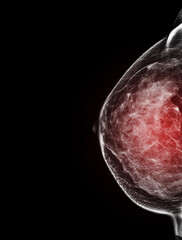

본원에서 유방 초음파를 시행한 40대 여성의 사례 |

치밀유방으로 초음파상 5.4 mm되는 종괴가 발견되었고, 조직검사상 조기암으로 진단 받아서 수술하였고,

수술 후 진단은 암 전단계인 ADH(atypical ductal hyperplasia: 비정형 유관 증식증)으로 판명 되었습니다.